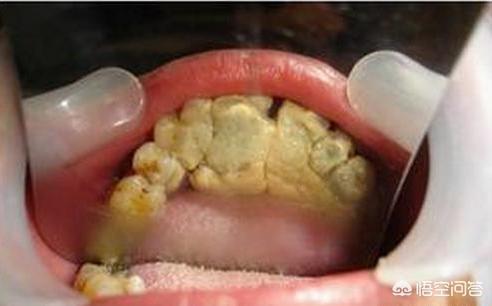

Zahnstein hat folgende Auswirkungen: Mundgeruch, Zahnverfärbung, Beeinträchtigung der zwischenmenschlichen Kommunikation, geschwollenes und schmerzhaftes Zahnfleisch, Karies, Parodontose, Zahnlockerung, -verschiebung, -abfall usw.

3. parodontale Erkrankung

Bleibt der Zahnstein bestehen, verschlimmert sich die Parodontitis weiter, was zu verschiedenen Komplikationen wie Zahnfleischbluten, Zahnfleischrückgang, Abbau des Alveolarknochens, Mundgeruch und anderen Beschwerden führt, und später haben die betroffenen Zähne keinen Alveolarknochen mehr und fallen nach dem dritten Grad der Lockerung von selbst aus.